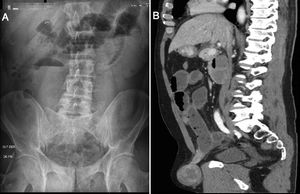

The patient is a 59-year-old man who consulted for symptoms of intestinal obstruction. Physical examination revealed an irreducible right inguinal hernia that was painful on palpation. Standing abdominal X-ray revealed dilation of the intestinal loops (Fig. 1A). Computed tomography scan showed a right inguinoscrotal hernia (Fig. 1B). Exploratory laparoscopy revealed a mass associated with the herniated intestinal loop (Fig. 2A). We performed the inguinal repair laparoscopically, and enterectomy of the intestinal segment associated with the tumor was performed through a midline mini-laparotomy (Fig. 2B). The postoperative recovery transpired without complications. The patient was discharged from hospital on the 4th postoperative day. The pathology report identified the mass as a gastrointestinal stromal tumor (GIST).